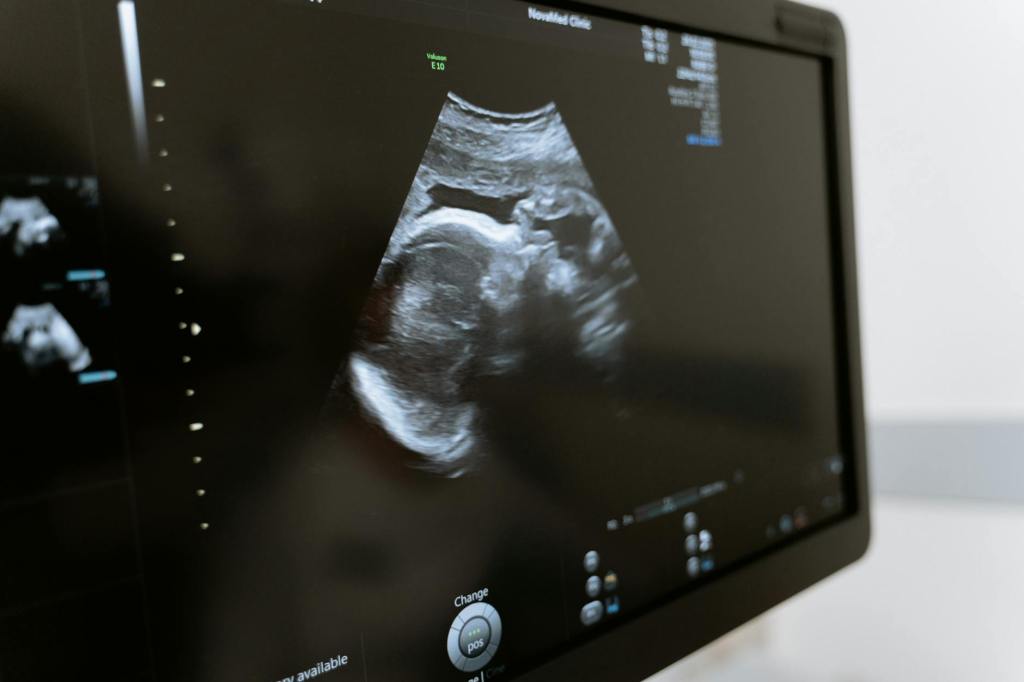

The Maternal Fetal Medicine (MFM) Unit at O&G SGH is the only specialized clinic in Sarawak dedicated to high-risk pregnancies. We receive referrals from hospitals and clinics across the state, providing expert care for both mothers and babies.

We offer a range of services to monitor and protect your baby during pregnancy, including:

- Detailed scans and screenings for high-risk pregnancies